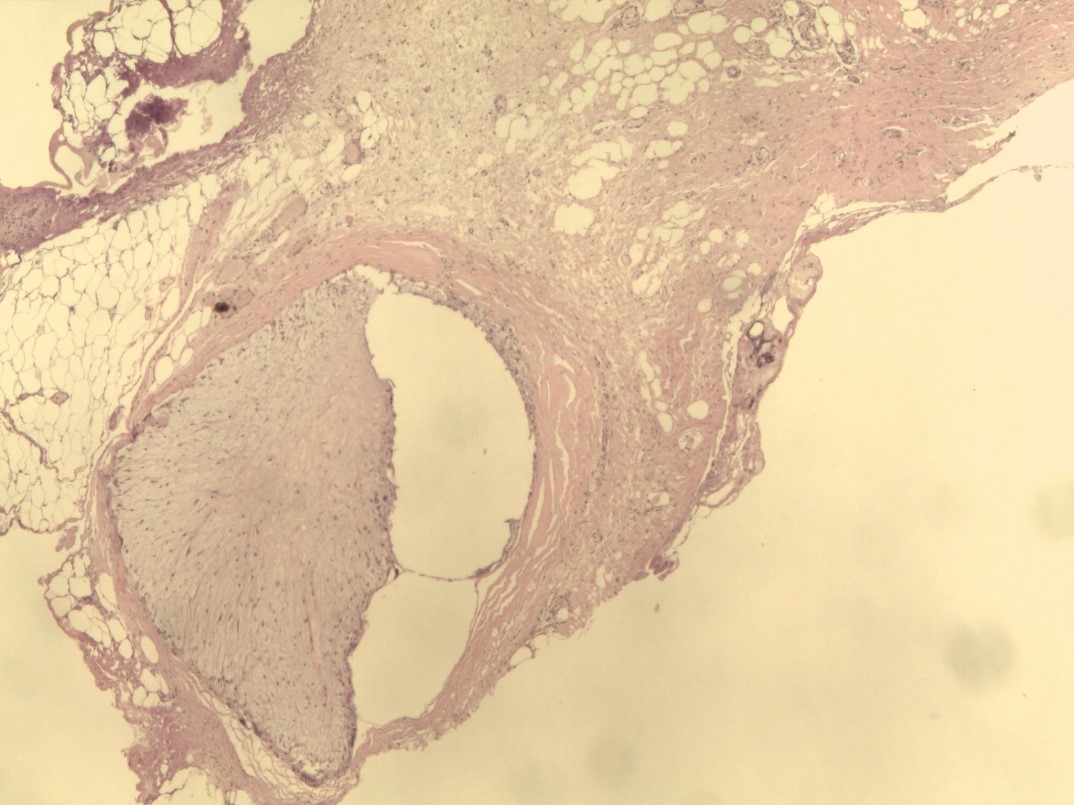

Гистологическая картина ПАМС до начала комплексного лечения была типичной и совпадала с описаниями других исследователей [22–26]. По всем полям визуализировали скопления гомогенных инородных тел (ПААГ), характер которых зависел от количества введенного геля, глубины и давности его залегания в мягких тканях, а также интенсивности его межтканевой миграции (рис. 1). Вокруг больших массивов безоболочечного имплантата, в основном сохранившего свою гомогенную базофильную структуру, прослеживалась тонкая соединительнотканная капсула толщина 50–120 мкм. Она состояла из нескольких слоев коллагеновых волокон и фибробластов (рис. 2). Толщина капсулы была неодинаковой на всем протяжении. На некоторых участках заметно выраженное ее истончение, разволокнение, дегенеративные изменения вплоть до полного перерыва (рис. 3). Последнее было особенно заметно у пациенток с длительным, свыше 10 лет, анамнезом «гелевой» болезни, а также при миграции ПААГ в соседние области.

Рис. 1. Биоптат ткани молочной железы: визуализируются скопления полиакриламидного геля диффузного и очагового характера. Окраска гематоксилином и эозином (×200).

Рис. 2. Биоптат ткани молочной железы: соединительнотканная капсула вокруг крупных очагов полиакриламидного геля. Окраска гематоксилином и эозином (×40).